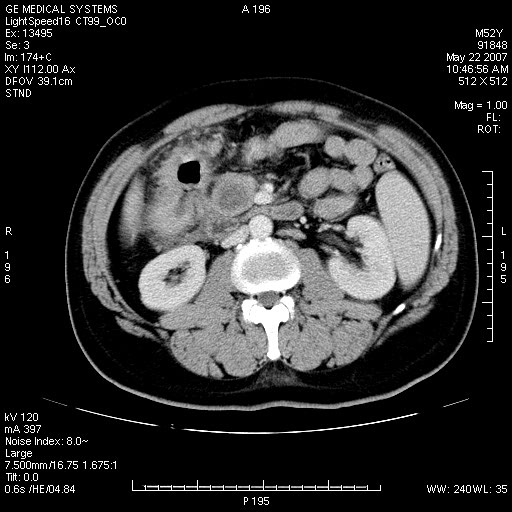

以下是引用余辉在2007-5-22 20:12:00的发言:[br]升结肠管壁明显增厚,增强有静脉期持续增强,结合患者病史,考虑结肠癌可能性大,临近脂肪影密度增高,混浊,恐有肠系膜浸润转移,建议镜检

以下是引用dyqct在2007-5-22 20:43:00的发言:[br]支持结肠肝曲占位性病变(浸润型结肠癌可能性大)。胆总管下端扩张,原因待查。

以下是引用gaoxiao在2007-5-22 20:49:00的发言:[br]考虑升结肠癌向周围侵犯,胰头钩突受侵。